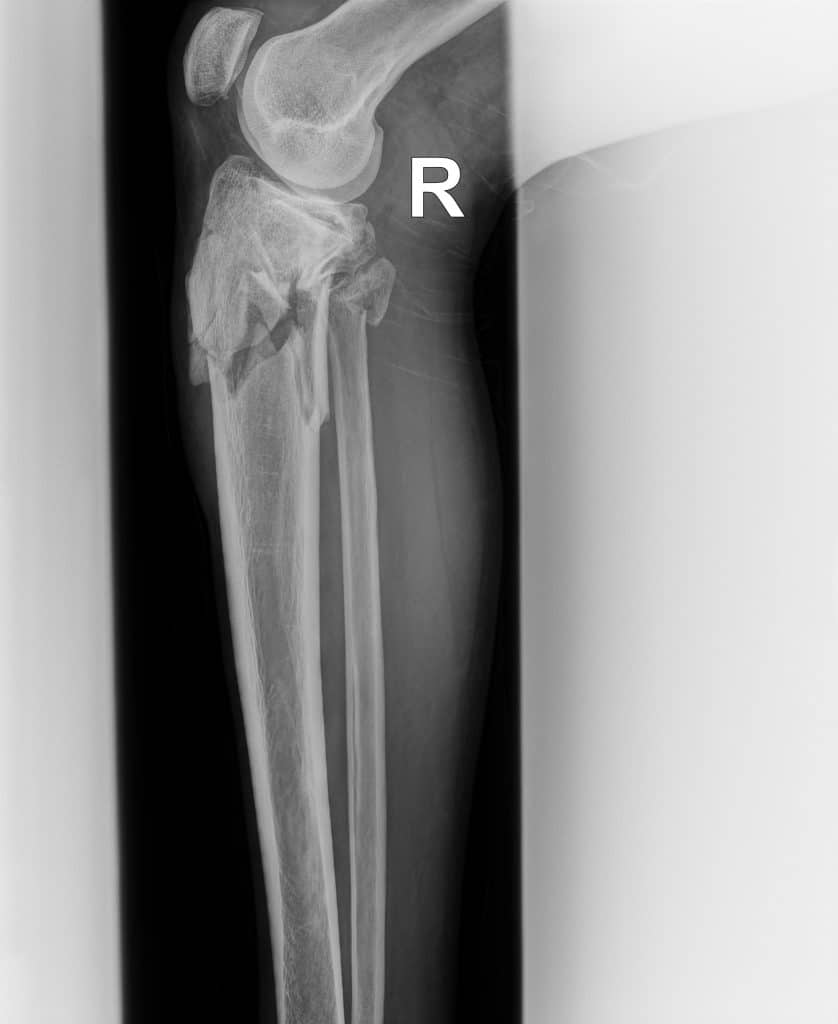

Bone images generated by spectral imaging emphasize calcified structures, allowing clinicians to review skeletal anatomy with reduced soft-tissue overlap.

The Bone image is more adept at presenting the bony skeleton in a manner that delineates it better than a conventional DR image. By displaying only on the areas of highest subject density, the SpectralDR™ technology yields improved visualization of both healthy and diseased bone.

SpectralDR bone images emphasize skeletal structures, allowing clearer visualization of the fracture compared with the conventional radiograph.